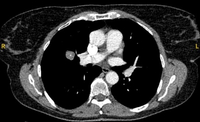

Computed tomography (CT) showing a posterior left upper lobe spiculated nodule, with ‘bronchus sign’ in a female non-smoker. Bronchoscopic forceps biopsy and brushing assisted by radial EBUS miniprobe localisation, confirmed a non-Hodgkin’s lymphoma

From the collection of Dr George Tsaknis, MD, PhD, FRCP(London), MRQA, MAcadMEd, PGCert; used with permission